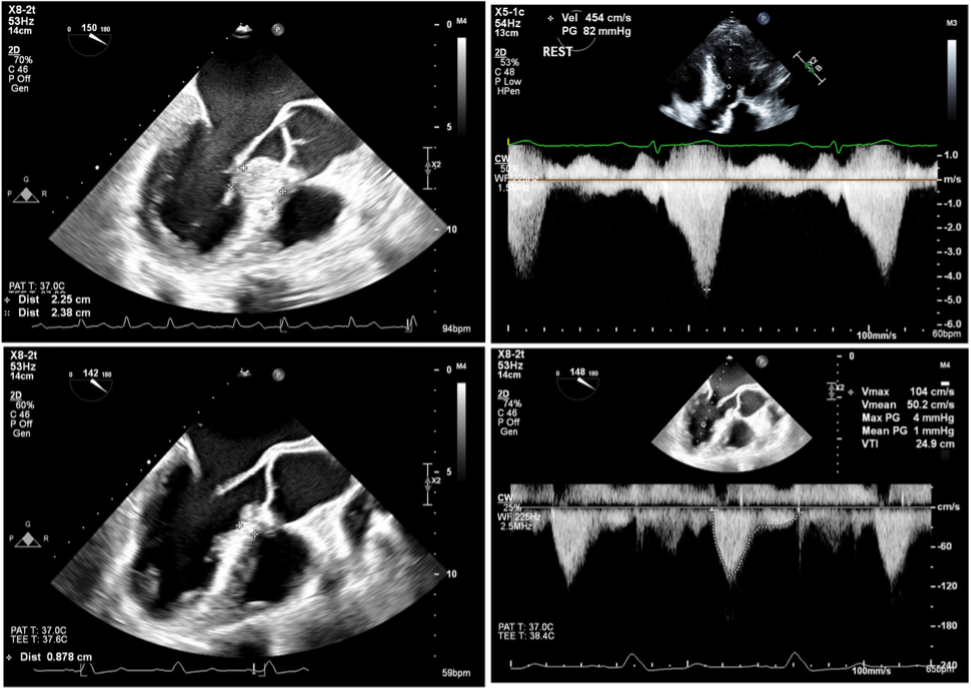

Given the patient’s significantly elevated left ventricular outflow tract (LVOT) gradient, along with his life-limiting symptoms and desire for a durable solution, he was an ideal candidate for surgical myectomy. In light of Dr. Scheinerman’s extensive experience with robotic cardiac operations, a robotic approach was offered for this curative procedure. It would represent the first robotic septal myectomy for obstructive HCM performed at NYU Langone.

Turning to the mitral valve, an incision was made in the anterior leaflet to expose the interventricular septum. Using robotic instrumentation, Dr. Scheinerman performed the septal myectomy from the basal to apical septum. The extent of resection was guided by preoperative transthoracic and transesophageal echocardiography as well as structural CT imaging. Approximately 10 mm in depth and 40 mm in length of septal myocardium was resected to achieve adequate relief of LVOT obstruction.

Postoperative transesophageal echocardiography demonstrated a superb result: significantly reduced septal thickness, absence of systolic anterior motion of the mitral valve, elimination of LVOT obstruction, trace mitral regurgitation, and no ventricular septal defect. The patient was discharged on postoperative day four.